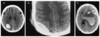

What is the average range of attenuation for each of the following (in the context of peritoneal effusion)?

- Bile, urine, intestinal contents

- Clotted blood

- Unclotted blood

- Bile, urine, intestinal contents: 0-15 HU

- Clotted blood: 45-70 HU

- Unclotted blood: 30-45 HU

What is the sentinel clot?

The highest attenuating hematoma (sentinel clot) is expected to be close to the site of bleeding. Lower attenuating unclotted blood is located farther from the source.